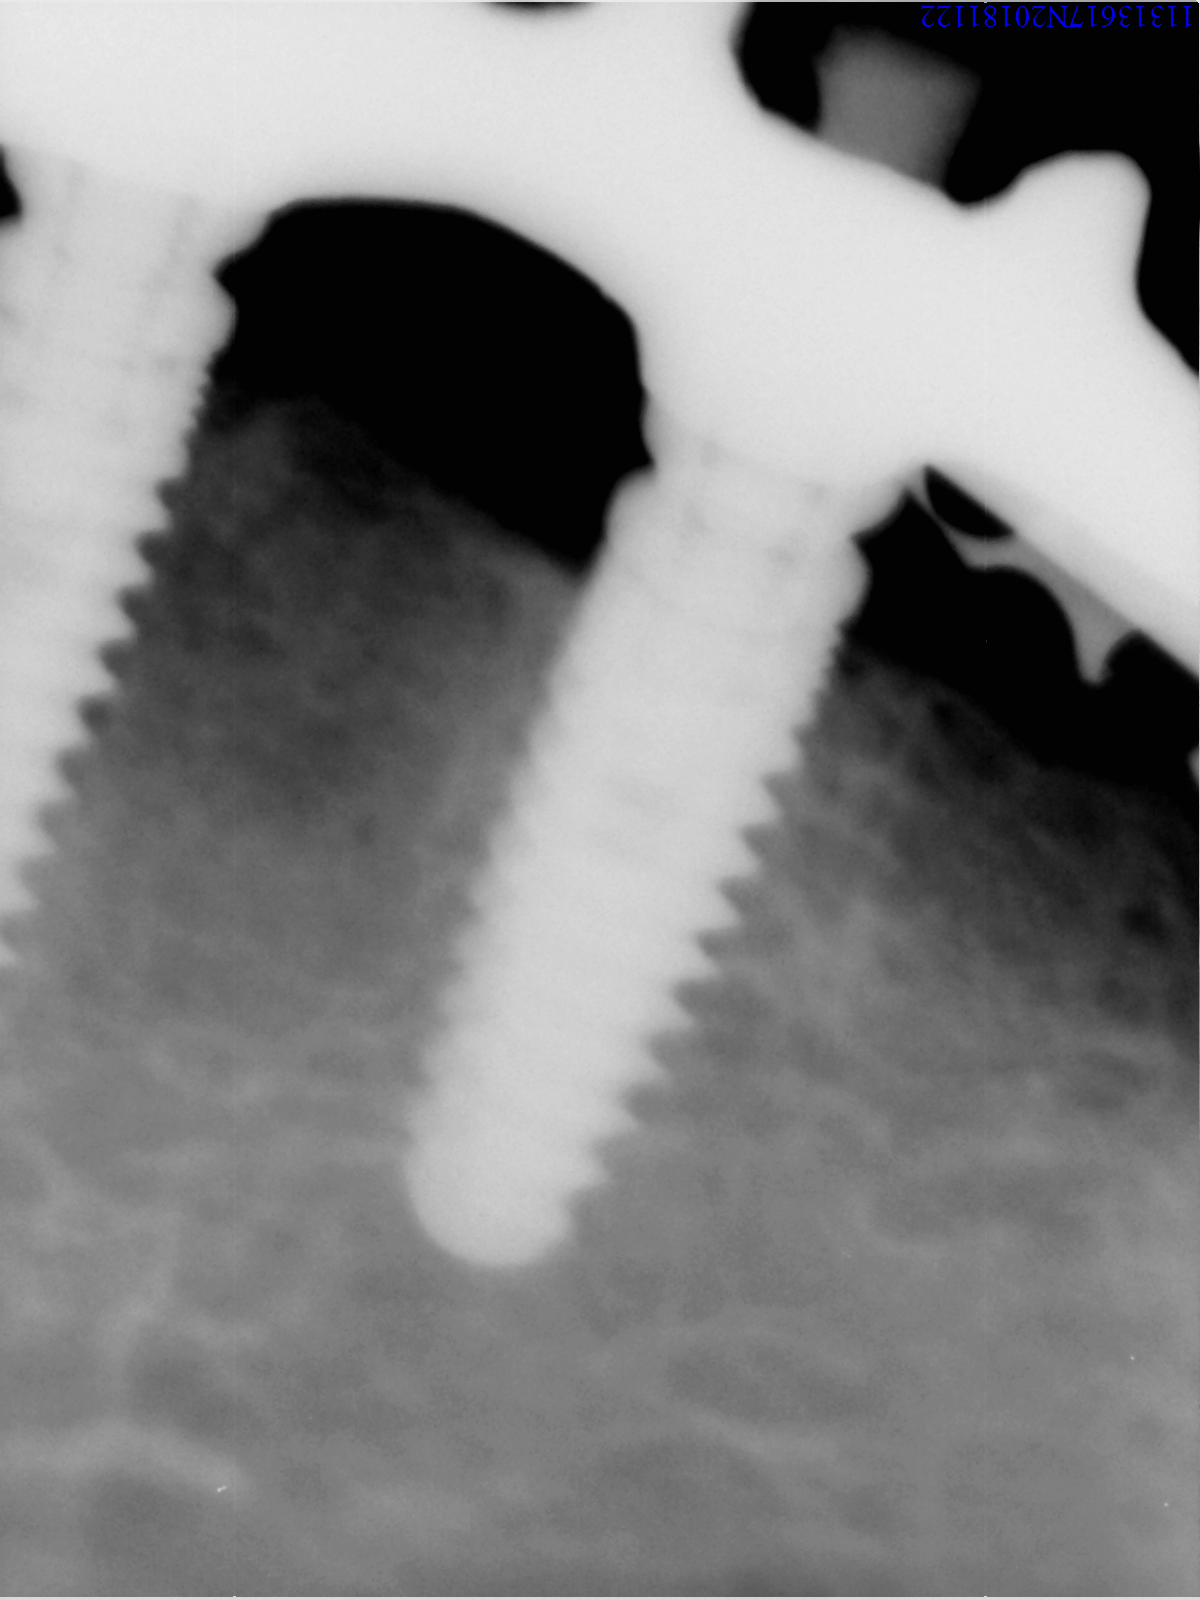

Conexión externa. Necesitamls saber el tornillo, es de rosca mas estrecha que phibo y 3i.

Es hexágono interno de solo 2mm de lado a lado del hexágono, no 2,4 como los de conexión tipo Niznick, lleva 25 años en boca según el paciente.